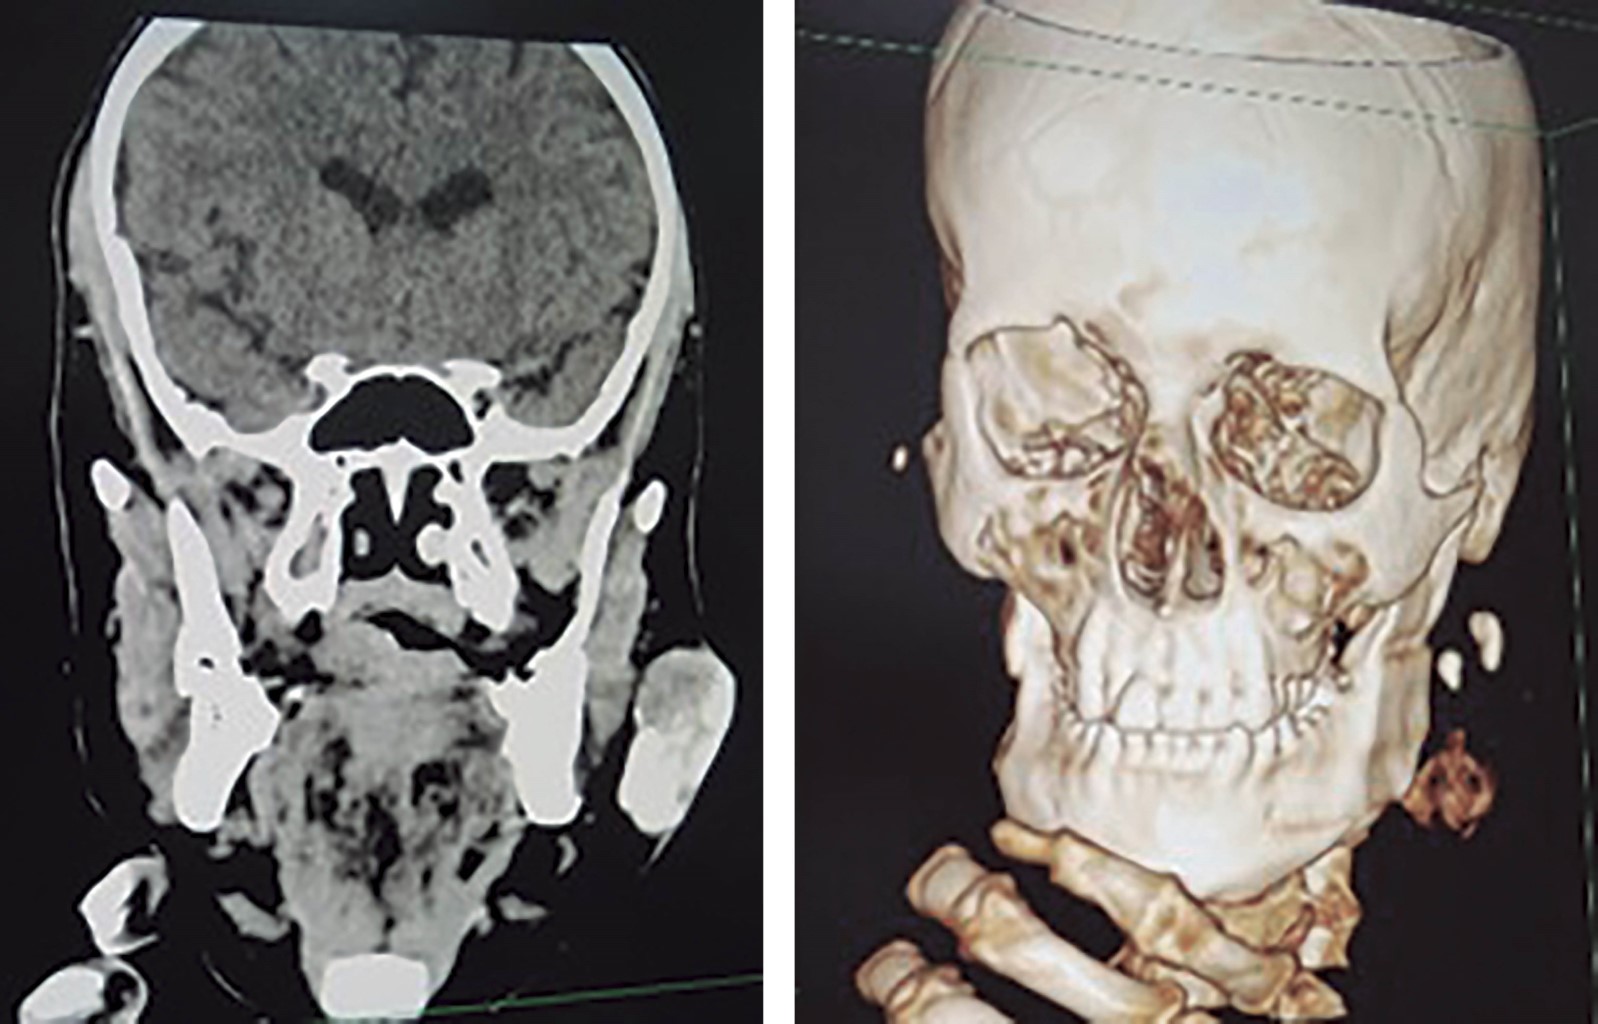

Pilomatrixoma is a slow-growing benign skin tumor described more than 130 years ago. Its name comes from the matrix of the hair follicle from which it derives, containing keratin, calcium and inflammatory tissue. The following is a clinical case of a 24-year-old male patient, with enlargement in the parotid region (a rare region) because it is located above the parotid gland, of nine years of evolution, with accelerated growth during the last year, becoming a giant pilomatrixoma, asymptomatic, with diagnosis and treatment for pilomatrixoma.

Figure 1

Figure 2

Figure 3

Figure 4

Figure 5